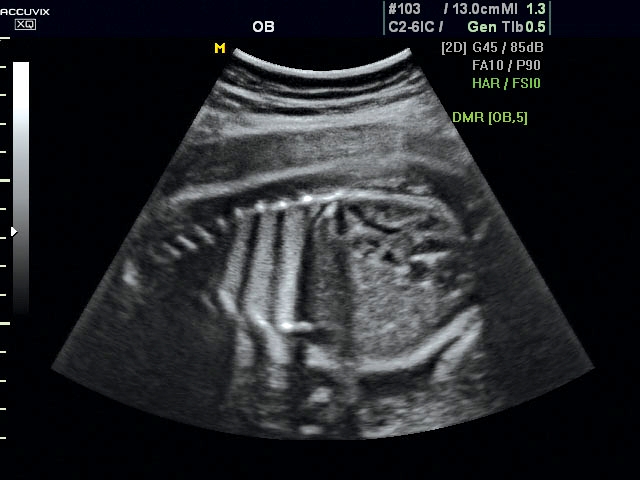

A pontos analízis és diagnózis iránti egyre növekvő igény kiszolgálására a MEDISON egy új real time képfeldolgozó technológiát fejlesztett ki Dynamic MR™ elnevezéssel. Az eljárás a diagnosztikus ismeretanyagot a precizitás és a pontosság egy teljesen új szintjére emeli. Használata az alapvető 2D ultrahang képinformáció real time, kivételesen kristálytiszta és kiemelkedően részletezett megjelenítését teszi lehetővé tűéles kontúrok és finoman rajzolt szövetstruktúra mellett. A DMR™ technológia ideális eszköze az ultrahang-diagnosztikának kezdve a szülészet-nőgyógyászattól a foetalis echon át az általános alkalmazásokig.

A DynamicMR alkalmazása az átlagos ultrahang teljesítményt a zaj és szemcsézettség jellegű műtermékek kiszűrése révén a vizuális diagnosztika, a precizitás és a pontosság új szférájába emeli. Figyelje meg a cerebellum, CSP és cisterna magna élstruktúráit, mennyire pontosan definiáltak és a teljes agyi struktúra ábrázolása a Dynamic MR alkalmazásával milyen látványosan javul.